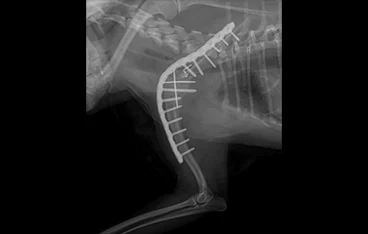

• 골반골절

• 골반골절 수술 전

골반골절 수술 후